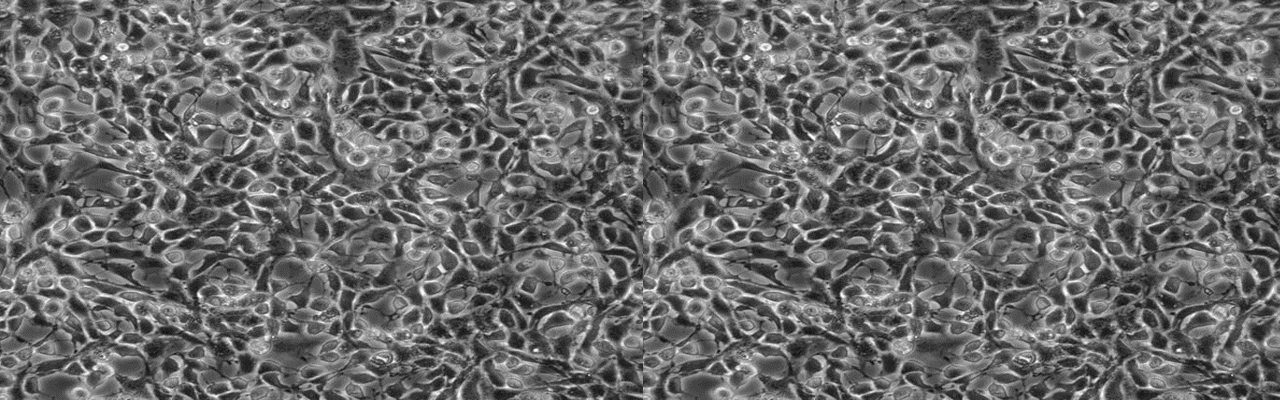

| 名称 | Lncap |

| 细胞全名 | 人前列腺癌细胞;Lncap |

| 生长特性: | 贴壁生长 |